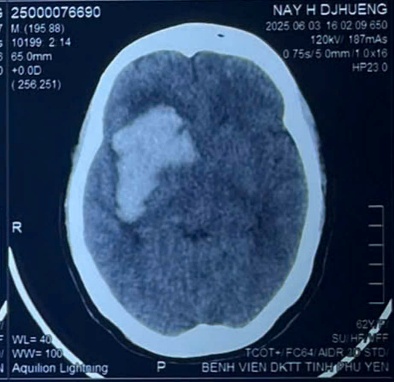

2.2. Xử lý các trường hợp đột quỵ não cấp: Phối hợp với các khoa liên quan để điều trị toàn diện. Phẫu thuật lấy máu tụ hoặc mở sọ giải áp khi có chỉ định các ca xuất huyết não, nhồi máu não,…

Phẫu thuật lấy máu tụ nội sọ